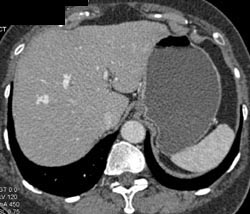

Av Shunt in Liver